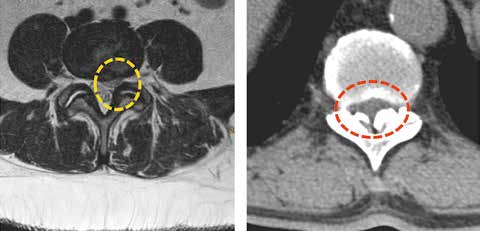

Mechanische Bedrängung der nervalen Strukturen

Kommt es bei einem Bandscheibenvorfall zu einer Nervenwurzelbedrängung, so kann durch entlastende und stellungskorrigierende Orthesen eine Beschwerdelinderung herbeigeführt werden. Die Industrie hat auf diese Pathologien mit „abrüstbaren“ Orthesen reagiert. Einer anfänglichen suffizienten Entlordosierung folgt eine Abrüstung der Orthese auf eine Bewegungslimitierung und anschließend Bewegungsfreigabe. Dieses Konzept ist auch mit dem aufgezeigten Vorgehen entsprechend dem Wolff’schen Gesetz stimmig und in sich logisch nachvollziehbar.

Dies ist aber nur dann sinnvoll, wenn eine sich ändernde Pathologie mit Besserungstendenz besteht. Nervenwurzelbedrängungen durch osteophytäre Ausziehungen etc. sind diesem Behandlungskonzept nicht zugänglich. Schmerzbehandlungen mit intraforaminellen Infiltrationen, Hiatus-sacralis-Infiltrationen oder auch nur Facetteninfiltrationen können in Kombination mit Orthesen in ihrer Effektivität gesteigert werden. Besteht hingegen bereits eine Spinalkanalstenose, so sind die Möglichkeiten der Orthesenversorgung ausgeschöpft (Abb. 7).